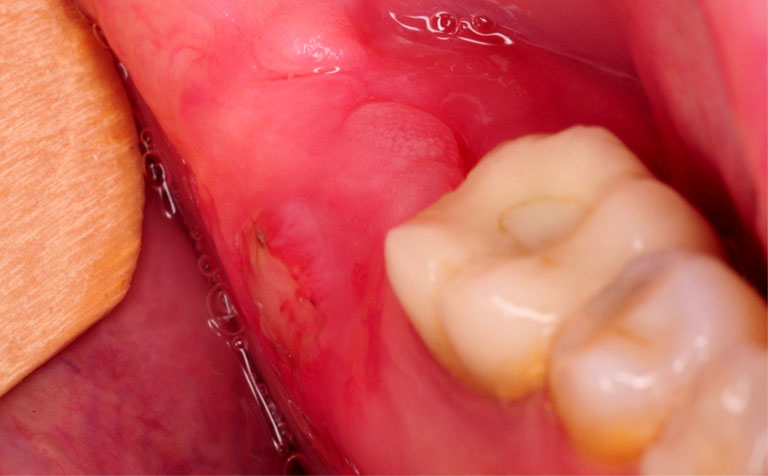

Răng khôn khi mọc sai vị trí, mọc lệch sẽ gây ra các triệu chứng như: đau nhức, sưng đỏ, u nang ở răng, viêm nhiễm, nhiễm trùng lặp đi lặp lại và thậm chí còn làm ảnh hưởng xấu đến các răng kề cạnh.

Răng khôn mọc làm sưng lợi